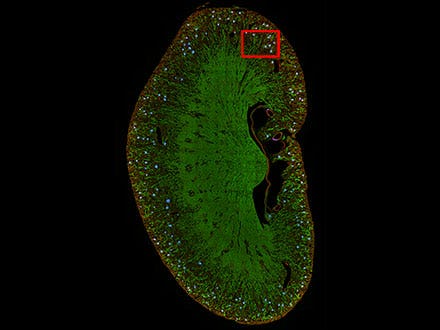

图6:利用TruAI(绿色)预测有丝分裂细胞。

图6

图7:虽然可以看到很多细胞,但只能检测到分开的细胞(右)。

4) 组织标本分割

TruAI也可用于分割组织标本。例如,肾小球难以使用常规方法进行区分,但可以使用TruAI进行细分。

图8:利用TruAI(蓝色)预测小鼠肾脏切片上的肾小球位置。

图8

图9

图9:TruAI捕捉并识别肾小球特征(右)。